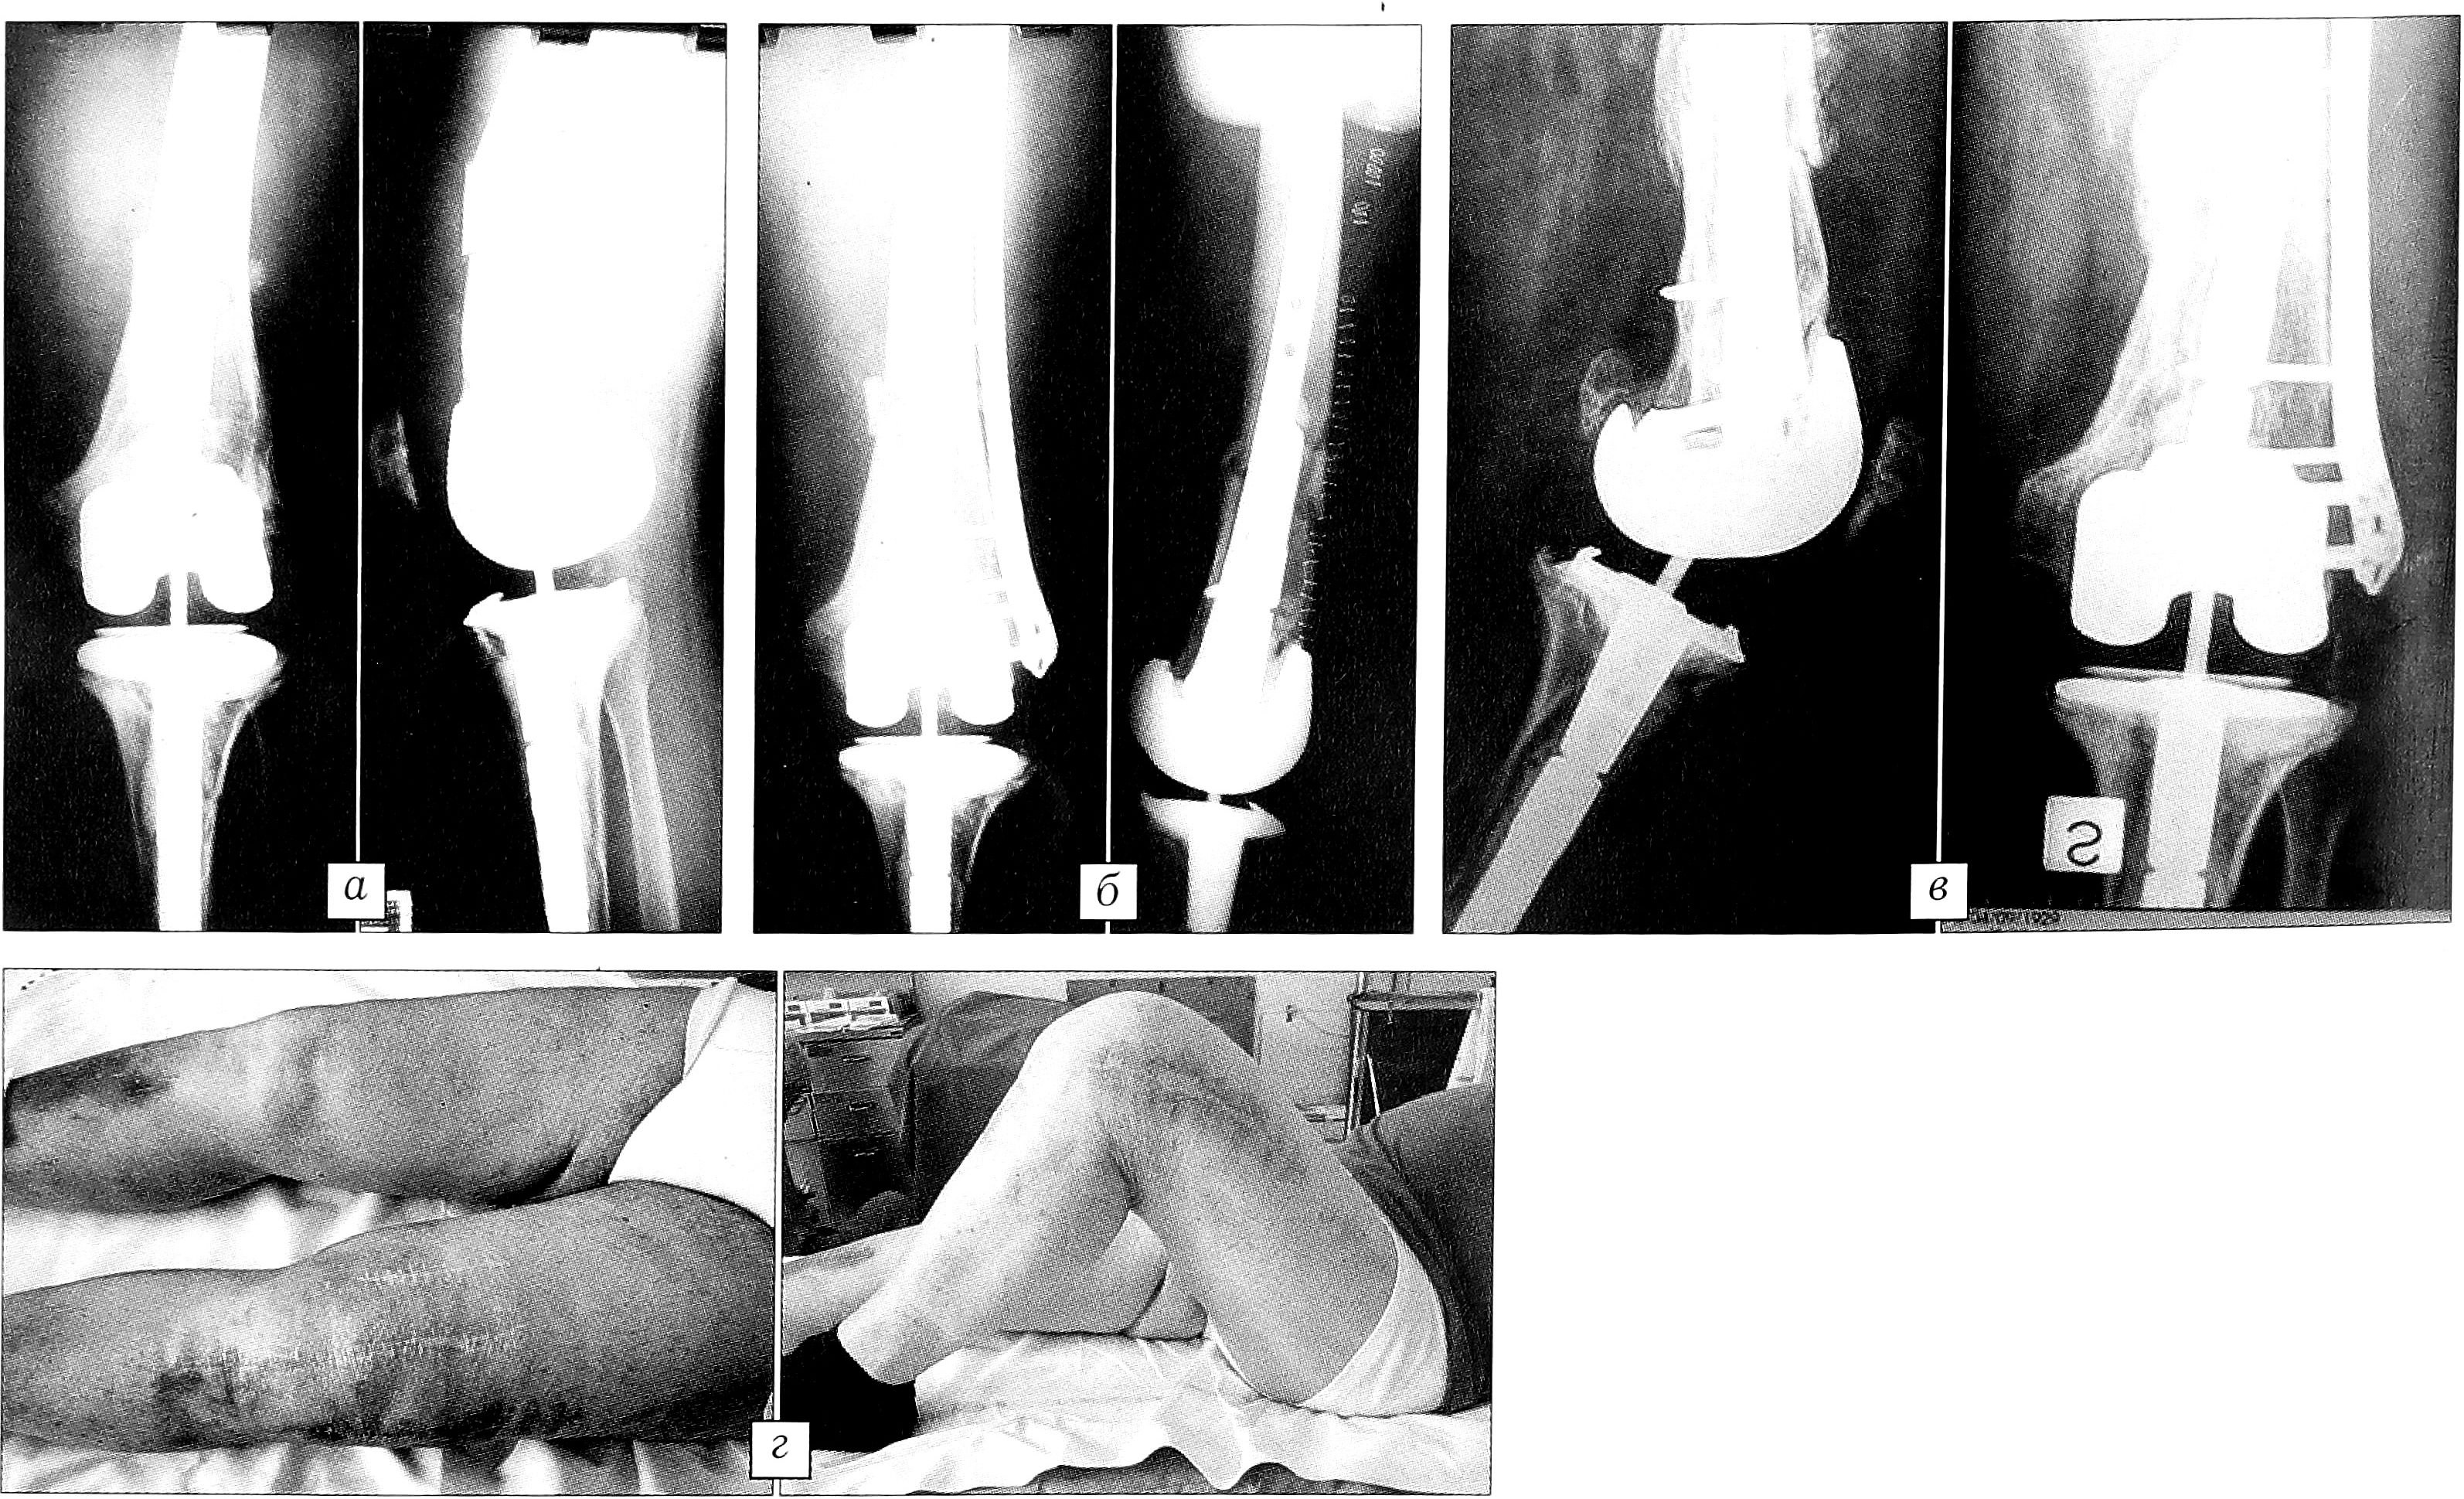

Больной Y.,72 лет. «Околопротезный» перелом (в анамнезе — тотальное эндопротезирование коленного сустава). Травма получена при падении с высоты собственного роста. Остеосинтез пластиной LISS «13 отверстий». Контроль через 3 мес: определяется костная мозоль, хорошая соосность. Контроль через 1,5 года после операции: обем движений в коленном суставе 0-100° (рис. 5).

Рис. 5. Больной Y. 72 лет. «Околопротезный» перелом в результате случайного падения. а — рентгенограммы перед операцией, б — после операции, в — через 6 мес после операции: определяется костная мозоль; г — контроль через 1,5 года после операции.